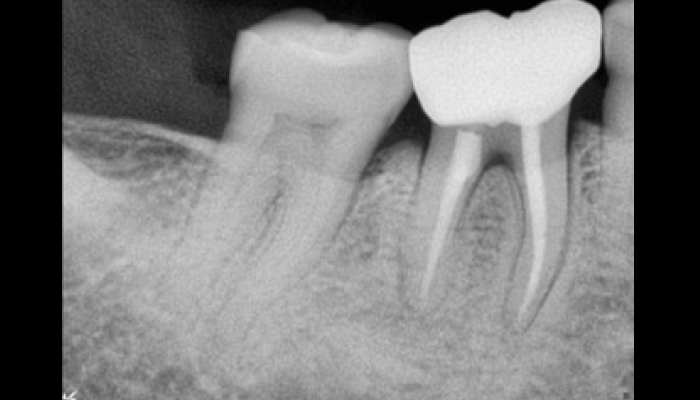

스케일링은 칫솔질로 제거되지 않은 치석과 치태를 제거하여 치석으로 인한 잇몸질환, 충치, 구취 등을 예방하는 치료입니다. 최근에 건강보험이 적용되어 1년에 한 번, 보험 혜택을 통해 스케일링을 받으실 수 있습니다.